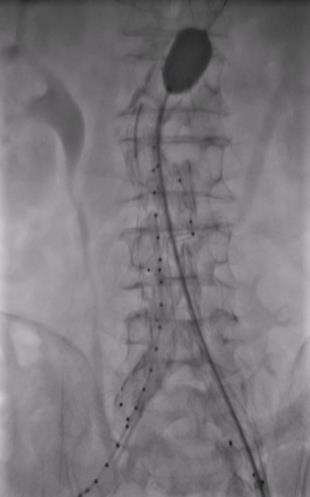

• Occult hepatocellular carcinoma presenting with humeral metastasis as the initial manifestation: a case report and literature review

2026, 35(1):141-148. DOI: 10.7659/j.issn.1005-6947.250622

Abstract (79) HTML (119) PDF 1.24 M (183) Comment (0) Favorites

Abstract:Background and Aims Hepatocellular carcinoma (HCC) presenting initially with bone metastasis is uncommon, and metastasis to the appendicular skeleton is particularly rare. These cases often lack typical liver disease history, elevated alpha-fetoprotein (AFP), or characteristic imaging findings, leading to frequent misdiagnosis or delayed diagnosis. This study reports a rare case of occult HCC presenting with humeral metastasis and reviews the literature to improve clinical recognition and management.Methods The clinical data of a 42-year-old male patient presenting with humeral metastasis as the initial manifestation admitted in August 2025 were retrospectively analyzed, including laboratory tests, multimodal imaging findings, histopathological and immunohistochemical results, treatment, and follow-up outcomes. Relevant literature was also reviewed.Results The patient presented with left shoulder pain. Imaging revealed osteolytic destruction of the left humerus. PET/CT incidentally detected multiple hepatic lesions without significant FDG uptake. Contrast-enhanced ultrasound demonstrated atypical enhancement patterns, initially suggesting a perivascular epithelioid cell tumor. Histopathological and immunohistochemical examination of biopsy specimens from both the humeral and hepatic lesions confirmed moderately differentiated hepatocellular carcinoma with humeral metastasis (CNLC stage IIIb). The patient received systemic therapy with sintilimab plus bevacizumab, followed by transcatheter arterial chemoembolization. After 6 months of follow-up, the intrahepatic lesions had decreased in size, the bone metastasis remained stable, and pain symptoms were significantly relieved.Conclusion HCC presenting with humeral metastasis as the initial manifestation is extremely rare and may lack typical imaging and serological features. Clinicians should consider HCC in patients with unexplained bone metastasis even in the absence of liver disease history or elevated AFP. Multimodal imaging and pathological biopsy are essential for accurate diagnosis and appropriate management.

• 0+1

• 1+1

• 2+1

• 3+1